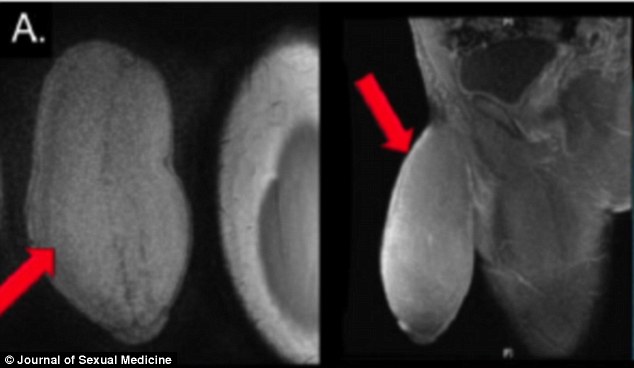

南佛羅里達大學泌尿科醫生凱瑞翁翻遍醫學文獻,都找不到陰莖縮小的前例可參考,只好採用治療陰莖海綿體白膜纖維化的佩洛尼氏病(Peyronie’s Disease)的手術方法,割開少年先前割包皮的疤痕,翻下陰莖皮膚,切下兩邊多餘組織,「像是為陰莖做抽脂手術」。

醫生術後並未丈量少年陰莖尺寸,不過,少年還是比一般男性的生殖器長、粗一點,形狀已經變得對稱,能正常勃起,也有感覺。